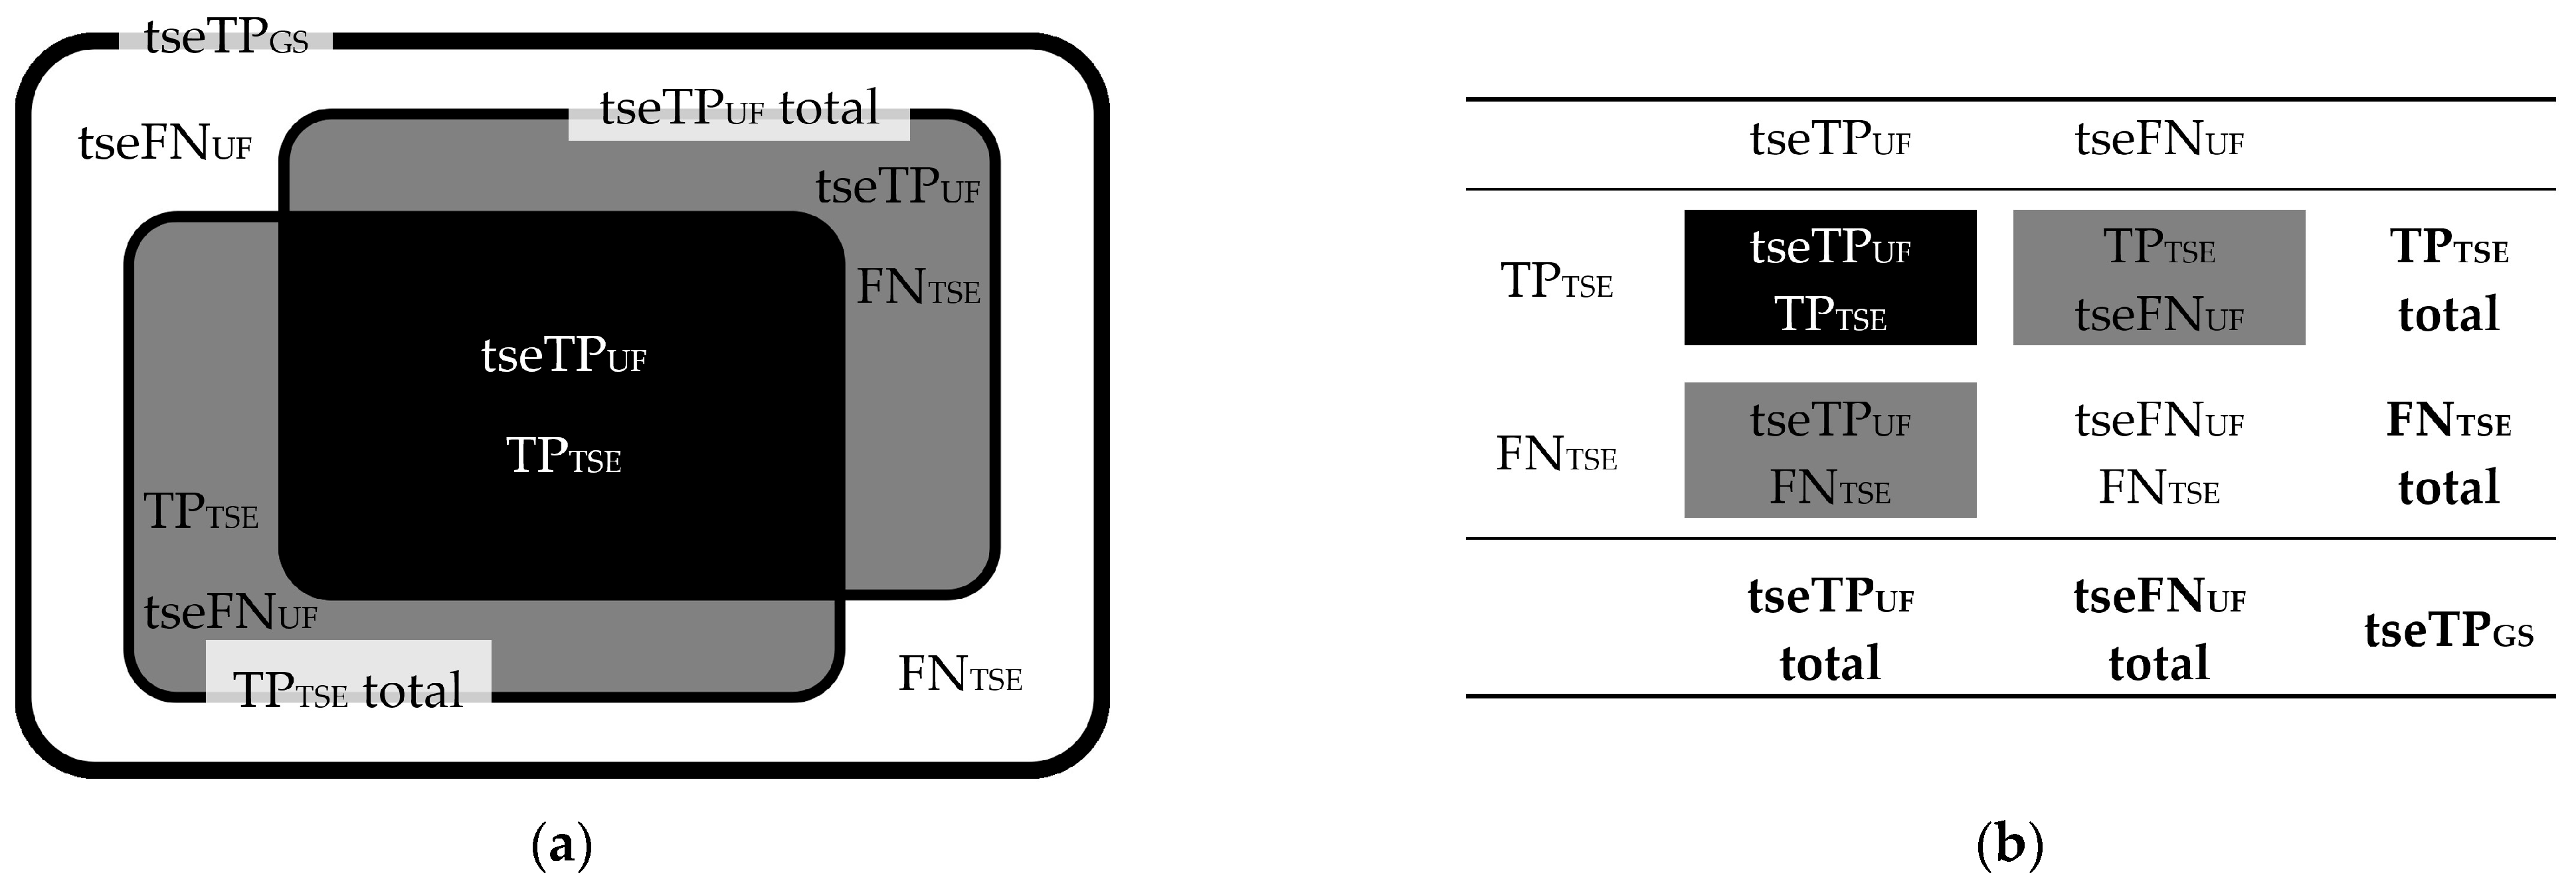

2.4.1. Lesion Assessment

3.2.2. FLAIRUF Compared with FLAIRTSE

3.2.3. Dependence on Size and Location within FLAIRUF